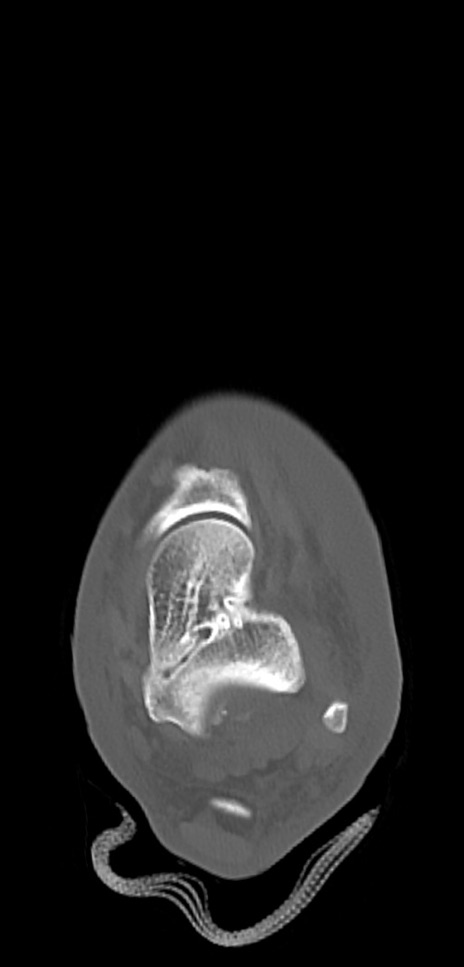

症例37 左足関節CT(横断像)

左足関節CT